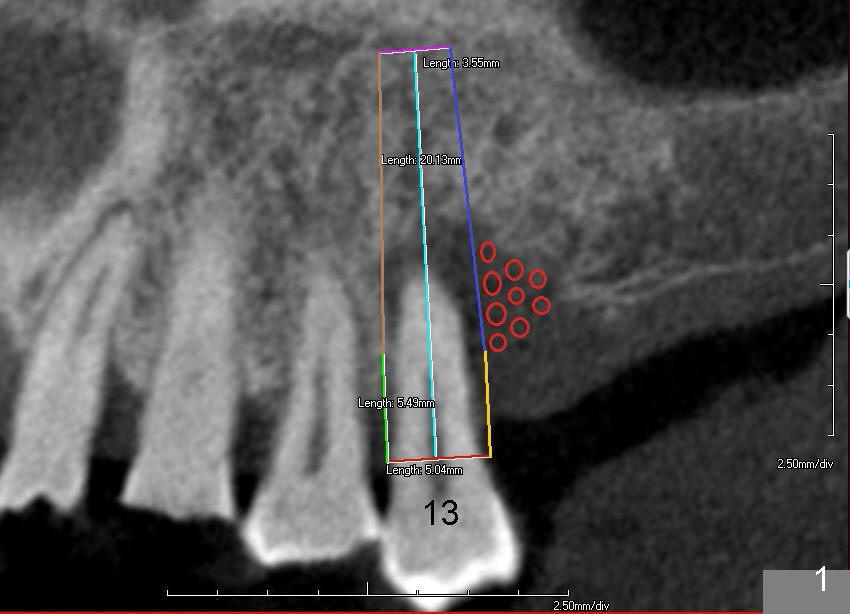

Immediate implant at the site of #13 is the last implant to be placed for full mouth reconstruction (Fig.1 CT sagittal section; 1 2 3 4 5 6 7 8). The sequence of the treatment is due to insurance benefit issues. In fact brackets for orthodontics were dislodged due to carelessness by the patient. He does not want to pursue this mode of treatment. Either prior to or after implant placement, bone graft will be placed distally (Fig.1: in large amount (red circles)) and buccally (Fig.2 (coronal section). If primary stability is acceptable, an immediate provisional is fabricated. He will be traveling abroad soon.

If the (mesio)distal bone resorption is less (Fig.1), D2 implant may be appropriate.

Fig.5 is an illustration showing the socket after extraction. The osteotomy is intentionally placed distally (Fig.6 arrow: pilot drill). In case the patient agrees to have ortho treatment, there will be space to correct the upper midline (7). If not, a molar crown will be fabricated. By the time a 4.5x20 mm tap is inserted (Fig.7 T), the mesial gap is visible (*). When a 6x20 mm implant is placed (Fig.8 I), bone graft is placed buccally (Fig.2, as planned) and mesially (Fig.8 red circles, as compared to Fig.1). The implant has to be as large and long as 6x20 mm to get primary stability (insertion torque 50/60 Ncm). The apex of the implant is close to the sinus floor (Fig.8 ^) or in fact the nasal floor (Fig.9 N). There appears bone growth in the mesial gap 3 months postop (Fig.10 *). There is no bone loss 2.5 years post cementation (Fig.11).